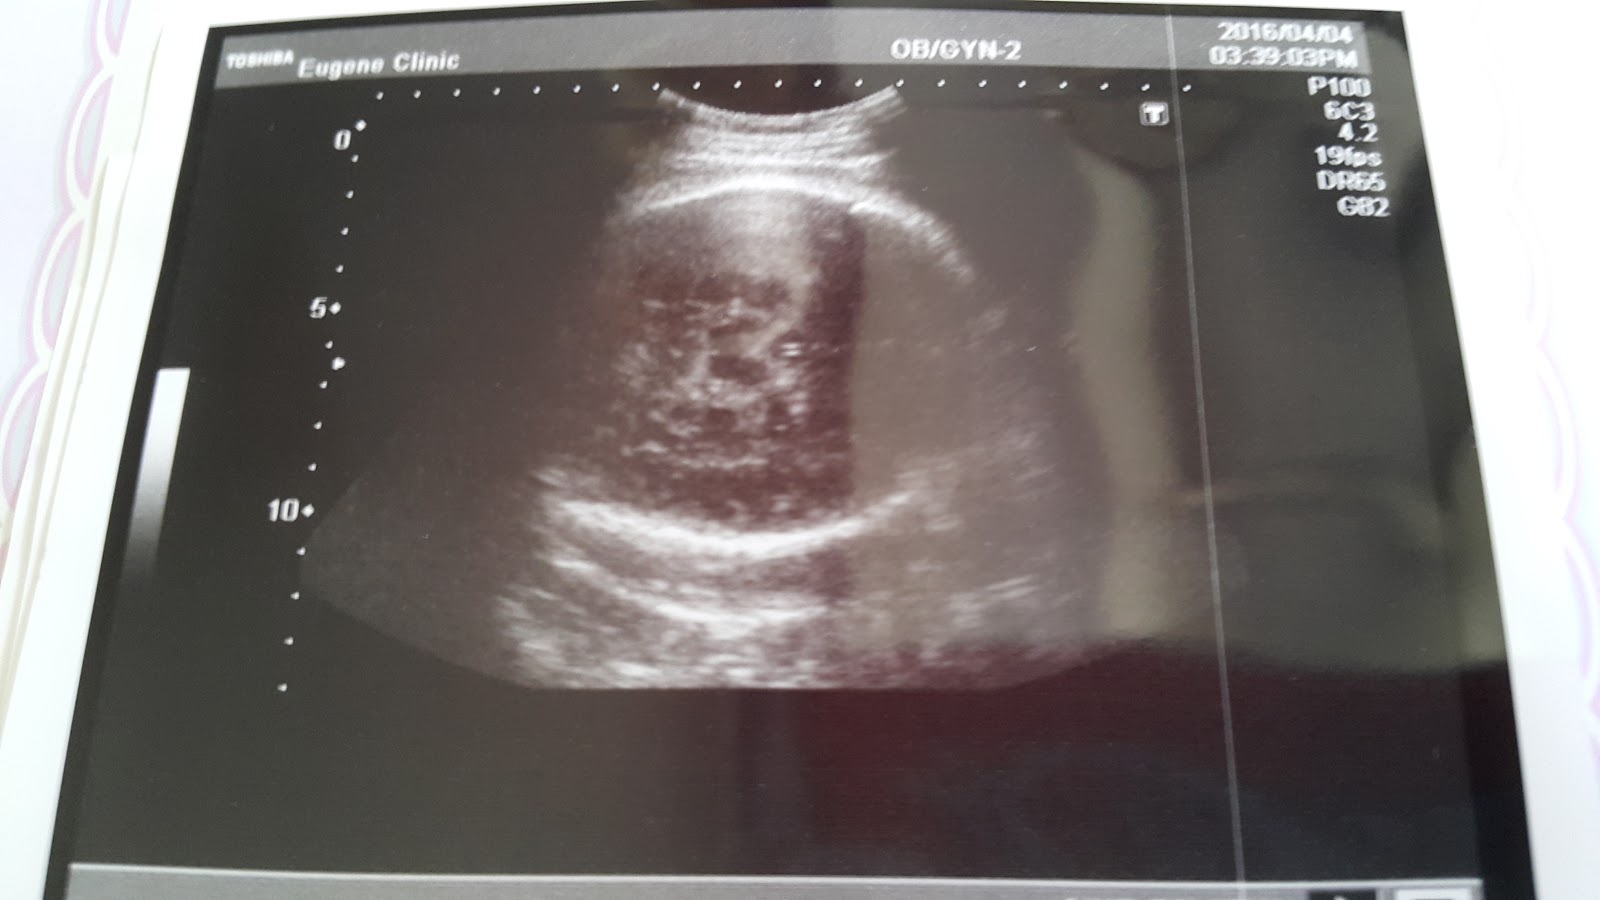

目前37w+4,做了第一次的宮縮測試

測大小、胎位、羊水足夠否等等,大約就是這樣

Haru baby現在已經大到沒辦法一次就看完全部,要分多次測量才能知道大小

目前Haru baby來到2840g,比哥哥大了許多,哥哥出生的時候才2750g呢!